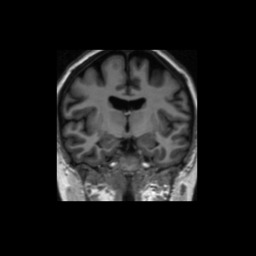

Accuracy is reported as Dice overlaps between a tool's segmentation and the Internet Brain Segmentation Repository (IBSR) manual segmentation for each of the 18 IBSR subjects. The inter-tool comparison (on the left below) shows the median Dice coefficient for each tissue class. The overlaps for FSL (from which the median values are drawn) are shown in the plot on the right.

Subject Accuracy (IBSR)

Overlap coefficients for each tissue class are shown here for each IBSR subject. Select a subject below to see the FSL results compared to other tools.